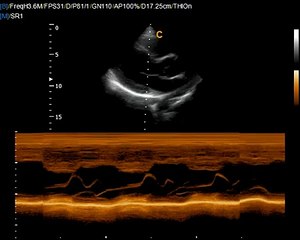

Q5 by Chison imaging Fetal Heart sonogram, easy to see heart in fetus, neonatal ultrasound